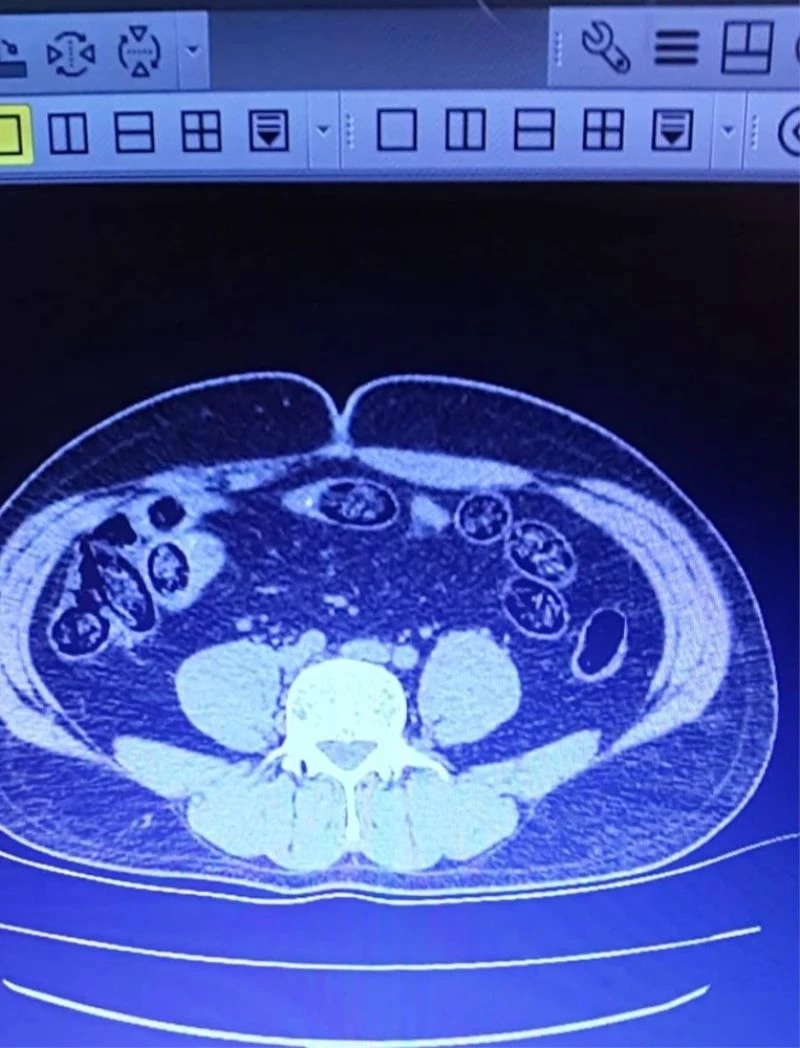

Van’dan uçakla İzmir’e gitmek isterken havalimanında yakalanan 2 İranlının yapılan muayenesinde toplamda 103 adet kapsül halinde 920 gram metanfetamin maddesi ele geçirildi.

Van Emniyet Müdürlüğünden yapılan açıklamada, Narkotik Suçlarla Mücadele Şube Müdürlüğü görevlilerince yapılan risk analizi çalışmaları neticesinde İran uyruklu A.D. ve S.A. isimli şahıslardan şüphelenildiği belirtildi. Açıklamada, “Şahısların Van-İzmir uçağına binişleri engellenmiş, alınan karara istinaden yapılan iç beden muayenesinde şahısların midelerinde kapsül halinde yabancı cisimler olduğu görülmüş. Yapılan iç beden muayenelerinden sonra taburcu edilmişler ve şahıslarda A.D.’den 52 adet kapsül halinde 460 gram, S.A.’dan ise 51 adet kapsül halinde 460 gram olmak üzere toplamda 103 adet kapsül halinde 920 gram metanfetamin maddesi ele geçirilmiştir. Elde edilen uyuşturucu maddeyle ilgili olarak gözaltına alınan A.D. ve S.A. isimli şahıslar, sevk edildikleri adli makamlarca tutuklanmışlardır” denildi.